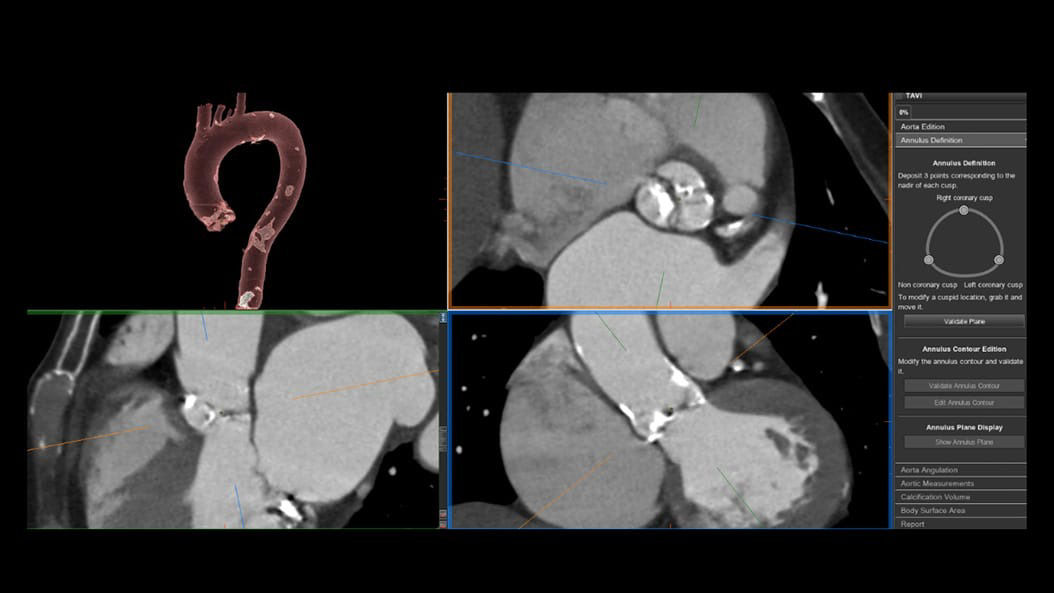

CT-Guided Interventional Care

Since becoming an important step in the patient care pathway and heart care guidelines, CT images are an invaluable tool in the cath lab, guiding procedures for precise personalized care.

Growth in CT imaging for structural heart (TAVR, TMVR, LAAO, etc.)⁴